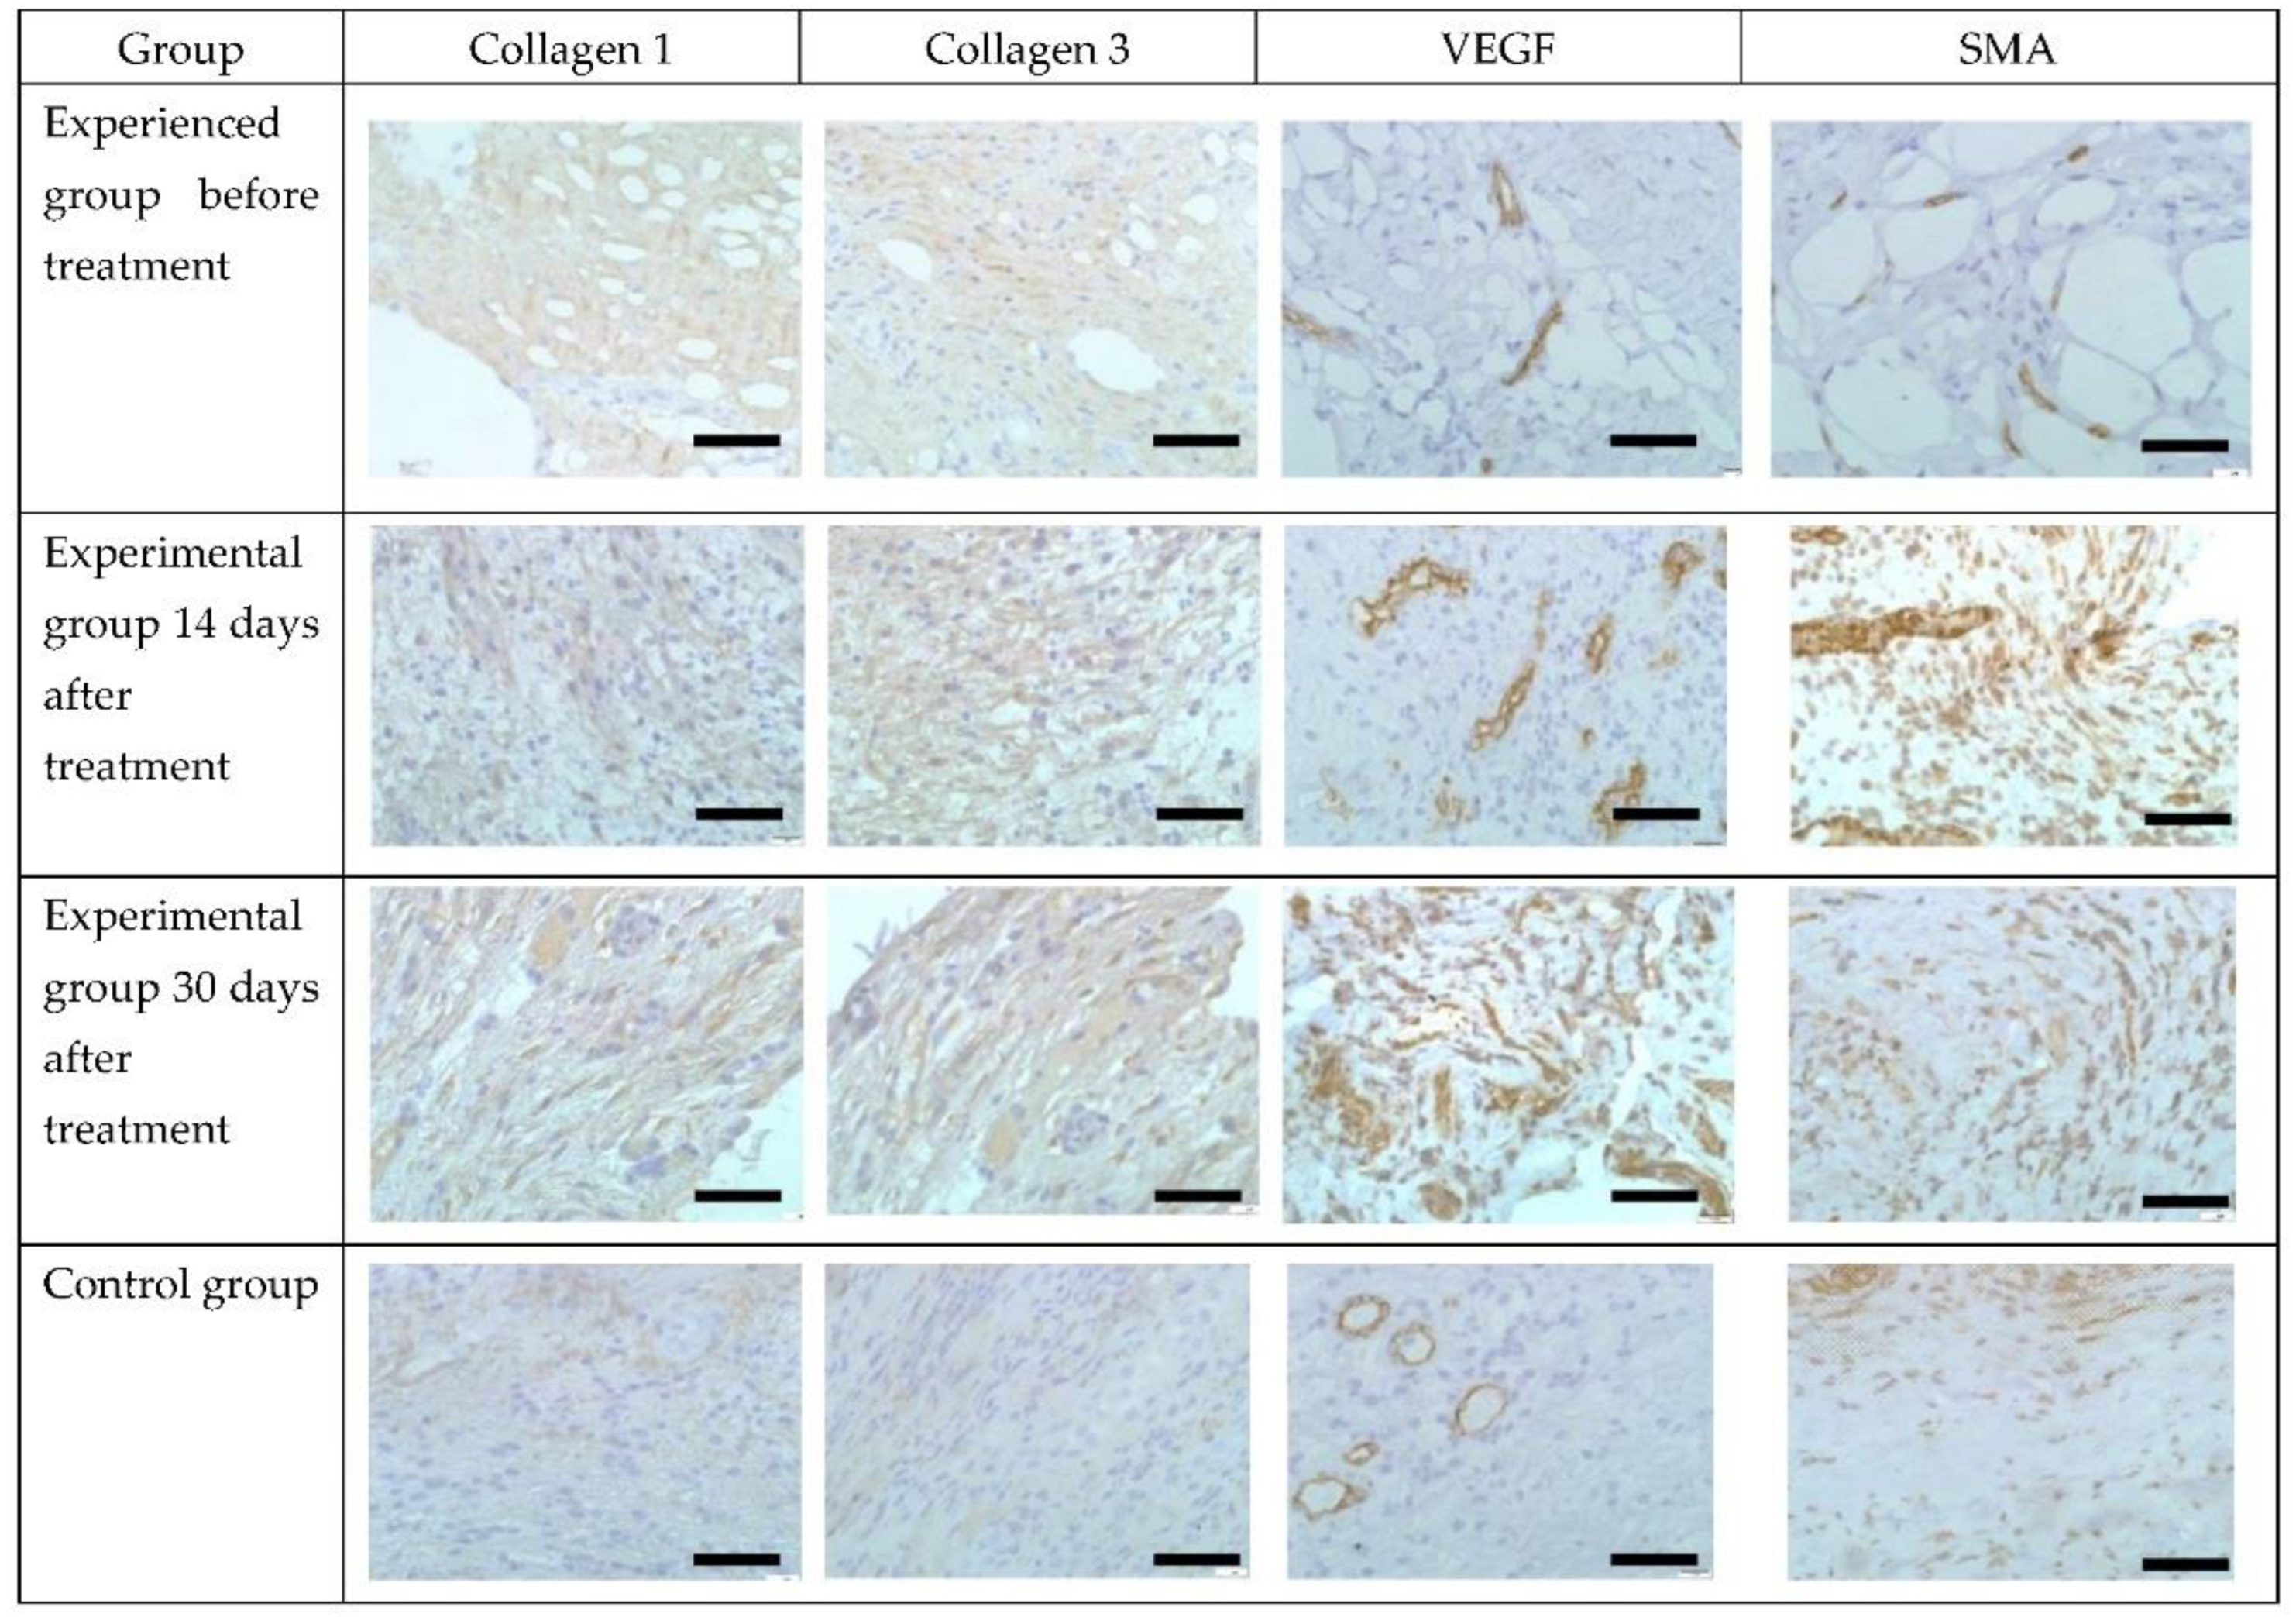

3.5. Bacteriological Analysis

| Collagen 1 (In Points) | Collagen 3 (In Points) | VEGF (% Positive Wound Stromal Cells) | SMA (% Positive Wound Stromal Cells) | |

|---|---|---|---|---|

| Experienced group before treatment | 0 | 0 | 15.0 ± 0.5 | 10.0 ± 1.0 |

| Experimental group 14 days after treatment | 4.0 ± 0.3 * | 4.0 ± 0.3 * | 30.0 ± 1.5 * | 60 ± 2.0 * |

| Experimental group 30 days after treatment | 6.0 ± 0.5 * | 6.0 ± 0.5 * | 70 ± 2.0 * | 30.0 ± 1.2 * |

| Control | 0 | 0 | 12 ± 0.5 | 15.0 ± 1.0 * |